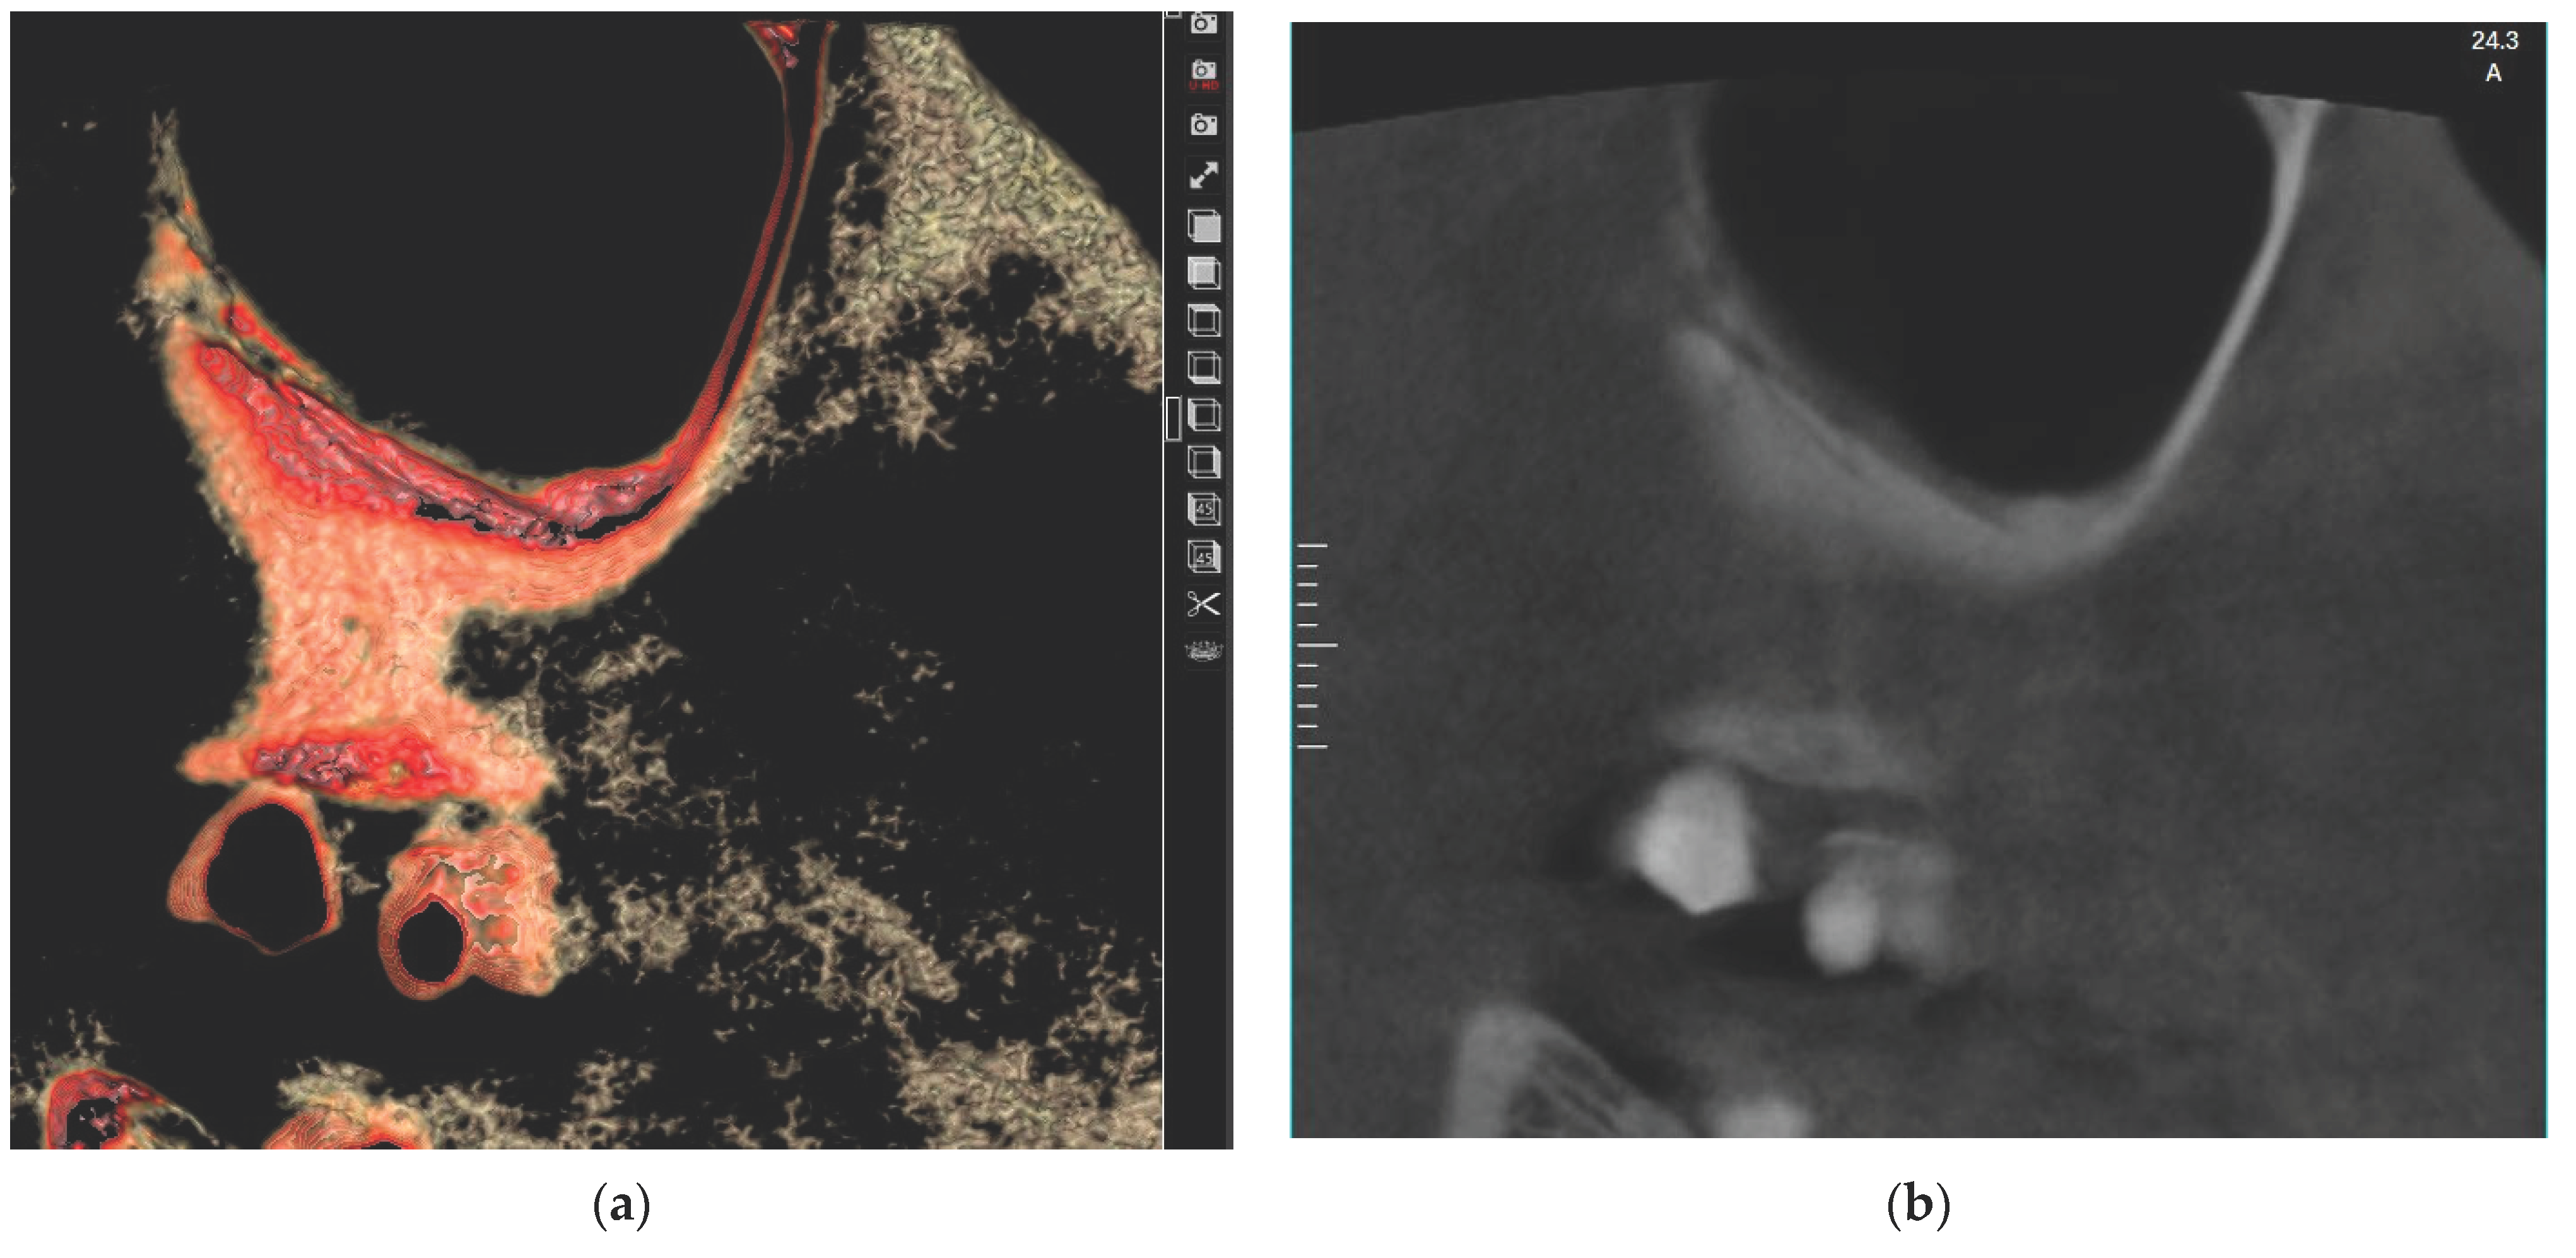

2.2. Radiographic Analysis